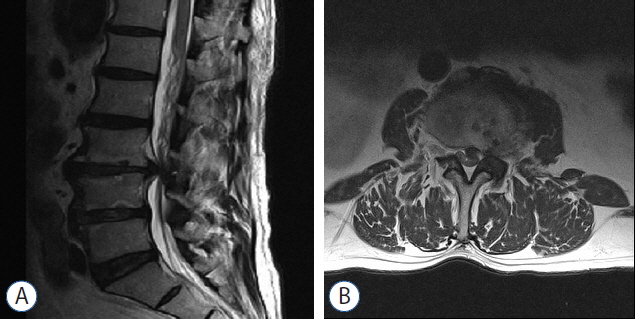

This study aimed to unravel the putative mechanism underlying the neurologic deficits contralateral to the side with lumbar disc herniation (LDH) and to elucidate the treatment for this condition.

From January 2009 to June 2015, 8 patients with LDH with predominantly contralateral neurologic deficits underwent surgical treatment on the side with LDH with or without decompressing the symptomatic side. A retrospective review of charts and radiological records of these 8 patients was performed. The putative mechanisms underlying the associated contralateral neurological deficits, magnetic resonance imaging (MRI), electromyography (EMG), and the adequate surgical approach are discussed here.

MRI revealed a similar laterally skewed paramedian disc herniation, with the apex deviated from the symptomatic side rather than directly compressing the nerve root; this condition may generate a contralateral traction force. EMG revealed radiculopathies in both sides of 6 patients and in the herniated side of 2 patients. Based on EMG findings and the existence of suspicious lateral recess stenosis of the symptomatic side, 6 patients underwent bilateral decompression of nerve roots and 2 were subjected to a microscopic discectomy to treat the asymptomatic disc herniation. No specific conditions such as venous congestion, nerve root anomaly or epidural lipomatosis were observed, which may be considered the putative pathomechanism causing the contralateral neurological deficits. The symptoms resolved significantly after surgery.

The traction force generated on the contralateral side and lateral recess stenosis, rather than direct compression, may cause the contralateral neurologic deficits observed in LDH.